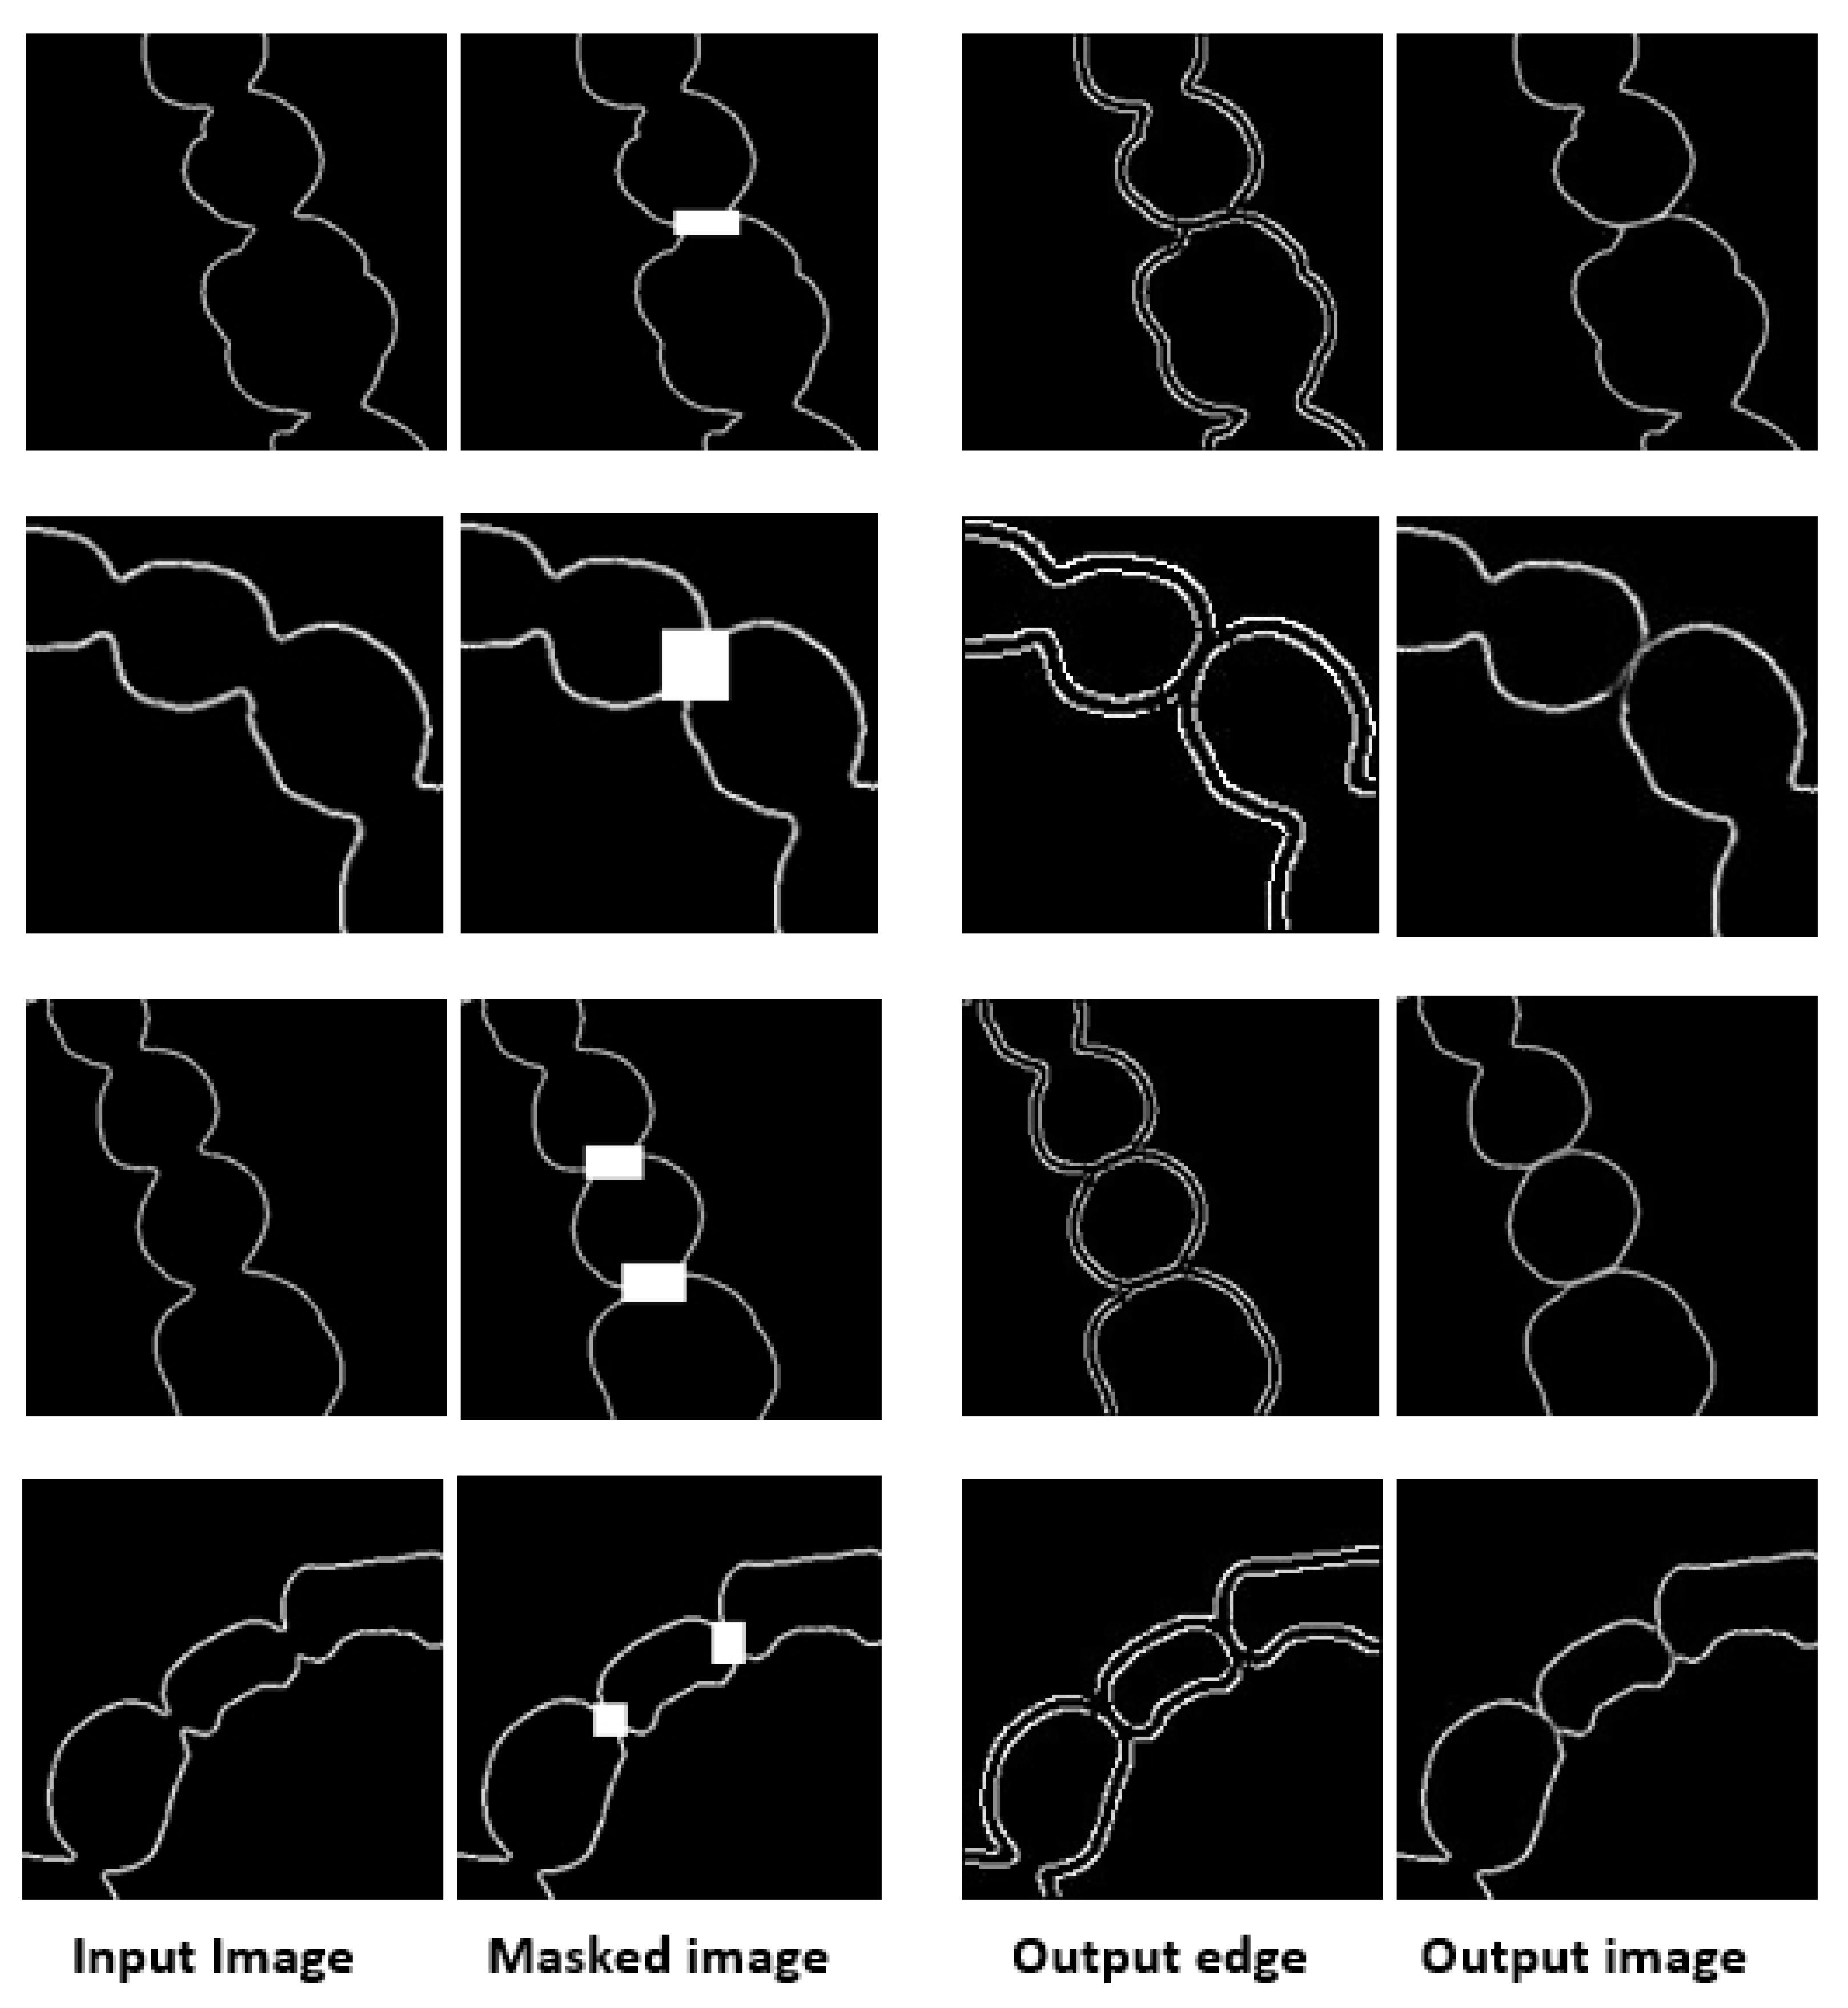

3.1. Result of Image Completion